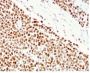

HCT116 or HeLa cell lysate (WB). Human colon carcinoma (IHC).

Antibody target cellular localization

Nucleus